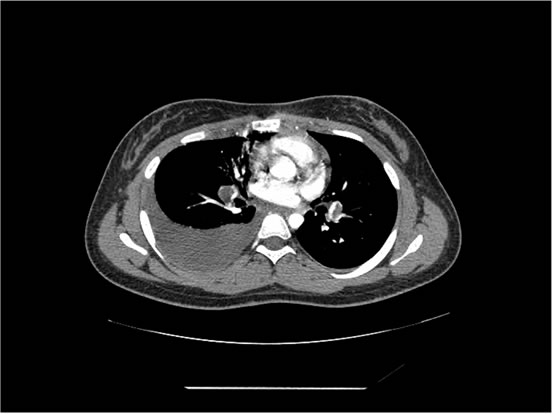

We ordered a CT scan with infusion of the chest

I will show you 12 CT-scan cuts.